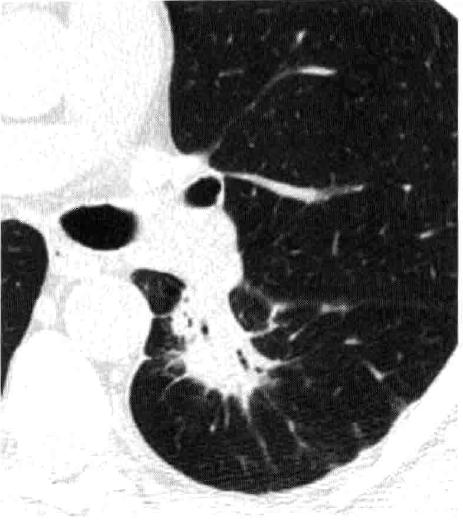

10) 肺窗和纵膈窗:顾名思义,肺窗就是专门看肺的,而纵隔窗则可以看纵隔(位于图像的中心部分,里面有你的小心心)及肺内实性成分(如淋巴结或病灶)。

肺窗

纵隔窗